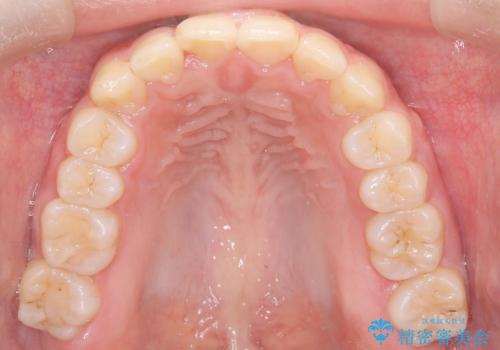

- 歯のデコボコ(叢生)を気にされて来院されました。精密な検査の結果、中等度の叢生と診断。患者様のご希望に合わせ、透明で目立ちにくい**インビザライン(マウスピース矯正)**による治療計画を立案しました。歯を抜かずに、歯列弓(歯が並ぶアーチ)を少しずつ拡大することで、歯が並ぶスペースを確保し、叢生を改善することを目指します。

今回の矯正治療では、透明なマウスピース型の装置インビザラインを使用しました。この装置は目立ちにくく、取り外しが可能なため、食事や歯磨きも普段通りに行えます。治療は、緻密に計算された治療計画に基づき、段階的に作製されたマウスピースを交換していくことで、歯列弓全体を徐々に広げていきました。この歯列弓の拡大により、不足していたスペースを確保し、歯のデコボコを効果的に解消。抜歯することなく、整った美しい歯並びと良好な咬み合わせを獲得していただけました。